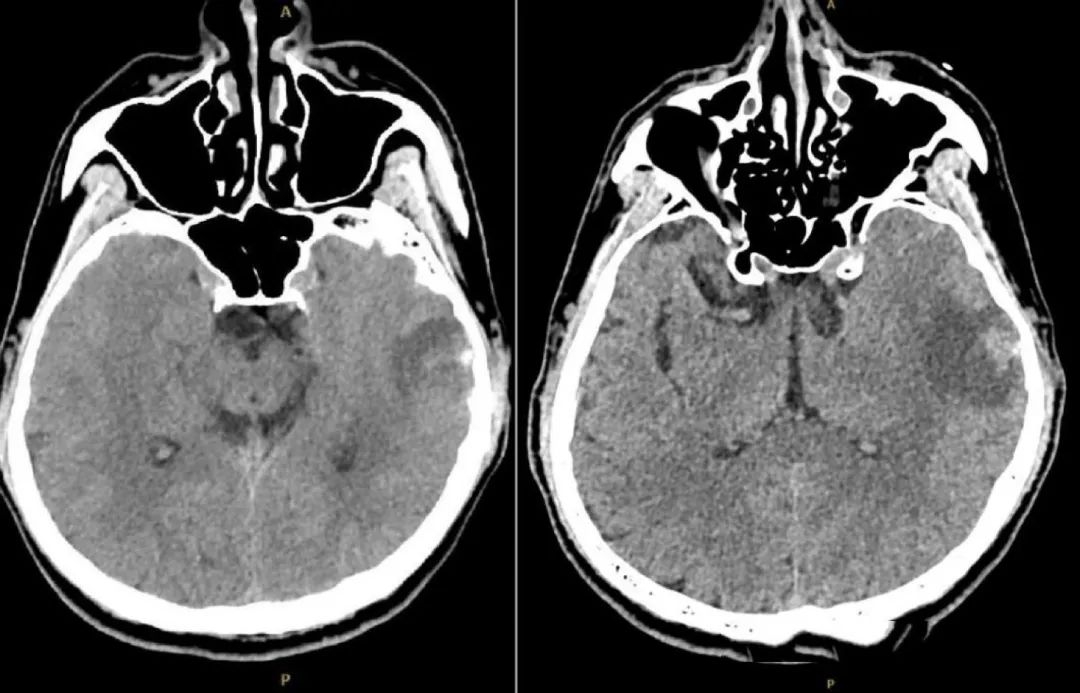

经检查,刘同学的大脑状态在短时间内急剧恶化,多处脑出血和肿胀、头颅CT血管影像中很多静脉血管消失。

图1. 头颅CT(发病后1周):左侧颞叶血肿可能。